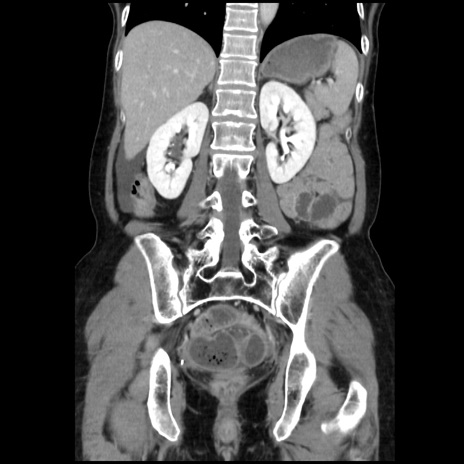

症例32(冠状断像)

【症例】40歳代 女性

【主訴】上腹部痛、嘔気・嘔吐

【現病歴】約9時間前頃から急に上腹部痛、嘔気、嘔吐が出現。改善しないため救急要請。

【既往歴】子宮頚癌(広汎子宮全摘術、放射線療法)、腸閉塞

【身体所見】腹部:平坦、軟、腸雑音亢進、上腹部を中心に腹部全体に圧痛あり。

【データ】WBC 8400、CRP 0.03